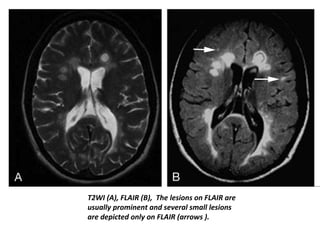

T2WI (A), FLAIR (B), The lesions on FLAIR are

are depicted only on FLAIR (arrows ).

• Owing tothe increased tissue contrast in FLAIR, it has improved detection of cerebral hemispheric lesions, especially increased sensitivity to the detection of juxtacortical lesions . • The improved tissue contrast of FLAIR images makes it overall easier to spot lesions at the first glance, probably one of the reasons why this sequence is often preferred over standard T2 weighted sequences.

T2WI (A), FLAIR(B), The lesions on FLAIR are usually prominent and several small lesions are depicted only on FLAIR (arrows ).